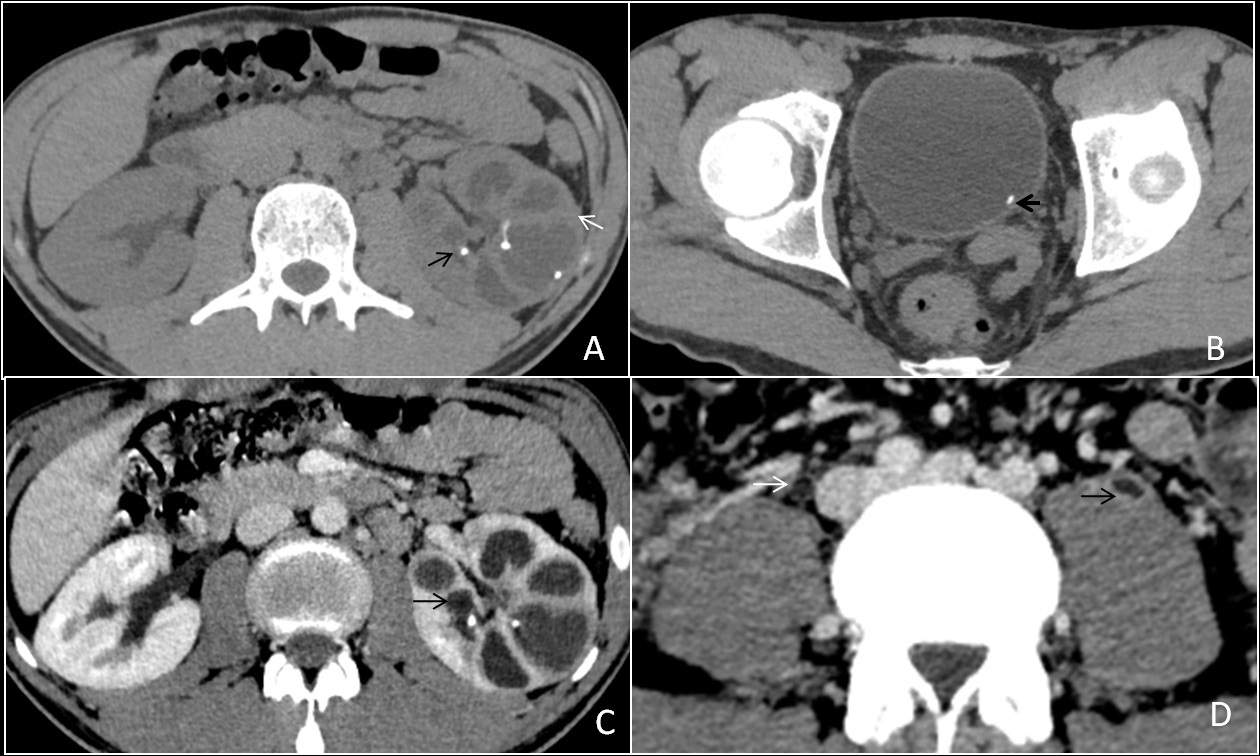

Genitourinary tuberculosis

Genitourinary tuberculosis is the second most common site of tuberculosis, caused by Mycobacterium tuberculosis, secondly to pulmonary tuberculosis. It can be divided anatomically into renal tuberculosis (renal parenchyma, calyces and renal pelvis), bladder and ureteric tuberculosis, prostatic tuberculosis, scrotal tuberculosis, tuberculous pelvic inflammatory disease (female). The kidneys are the most common site of GUTB. Clinical presentations are hematuria, frequency, urgency, dysuria with involvement of the bladder. Stricture formation is the most common complications in GUTB. Common sites of stricture formations are the neck of a calyx causing hydrocalyx, regional hydro calcinosis, pelvic-ureteric junction causing generalized dilatation of pelvicalyceal system and lower end of the ureter. Other imaging findings are parenchymal scars & irregularity of the papillary tips (motheaten calices), and small cavities in the papillae. (Figure 10A,10B,10C,10D) Sometimes fibrotic reactions may develop, leading to stenosis and strictures formations. Chronic tubercular infections in the genitourinary tract result in a ‘thimble bladder’ appearance and patulous VUJ (Figure 10E,10F). In females, pelvic tuberculosis is seen commonly in India, leading to a tubo-ovarian abscess or stricture formation (Figure 11A,11B).

Figure 10: (A) A 40 years old male patient came to our hospital three months back. After initial investigations, he was diagnosed with genito-urinary tuberculosis and started on ATT, after which the patient improved symptomatically. However, after three months, he discontinued the treatment and again presented to us with burning micturition and increased frequency of urination. The patient underwent a CT scan which is depicting a relatively enlarged left kidney with fine calcification along the calyces (black arrow) and thinning of renal parenchyma (white arrow). (B) NCCT scan at the level of the urinary bladder shows a focus of calcification in the urinary bladder near the left vesicoureteric junction (VUJ) (thick black arrow). (C) CECT scan in the axial plane at the corresponding level of the image (A) shows uneven caliectasis (black arrow). (D) Axial view from the CECT scan shows both mid parts of the ureters over the psoas muscle. There is dilatation of the left ureter and thickening and enhancement of the urothelial of the ureter (black arrow). The right ureter appears normal (white arrow). (E) A reformatted sagittal image of the venous phase from the CECT scan shows enhancing urothelial thickening of the left ureter, forming a lead pipe appearance (white arrow). (F) The reformatted sagittal image shows enhancing thickening of the urothelium of the left ureter up to the VUJ with a wide and incompetent VUJ. There is uneven dilatation of the upper calyx of the left kidney with no overlying renal cortex suggestive of phantom calyx and scar formation (white arrow). The urinary bladder has a “thimble bladder appearance” with a patulous VUJ (thick white arrow).